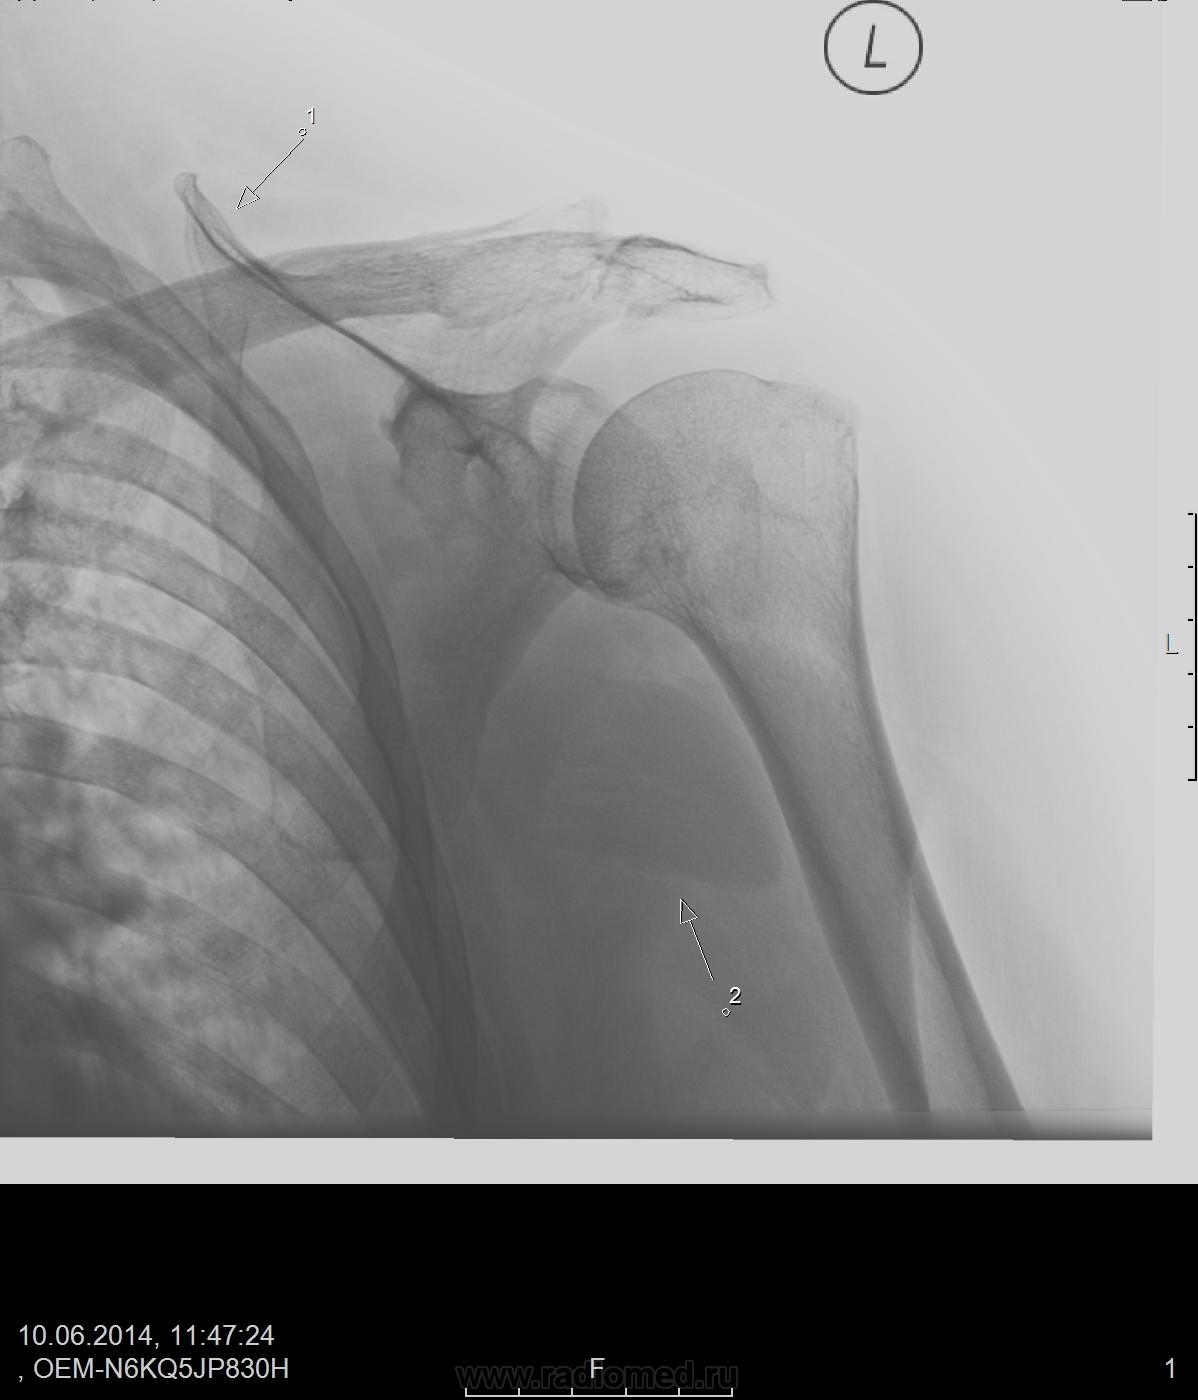

Старый сросшийся перелом акромиального конца ключицы. Стрелкой обозначен верхний край лопатки

Подвывиха ключицы в АКС точно нет, нижние поверхности примерно на одном уровне.

О лёгких судить трудно. Легочной рисунок смазан. Может, легочной венозный застой... На лёгкие надо делать снимок, как на лёгкие, заодно и с уплотнением, обозначенным стрелкой 2 разобраться.

в легких ничего не смущает?

Новообразование мягких тканей, с мтс в легкие...

пациентке 59 лет, жалуется на боль в суставе